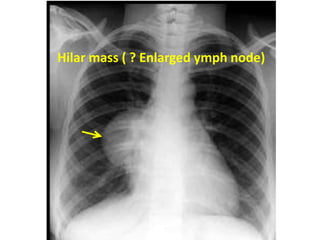

Hila

Note position and size bilaterally

Check for enlarged lymph nodes

Mass lesions

Hilar mass ( ? Enlarged ymph node)